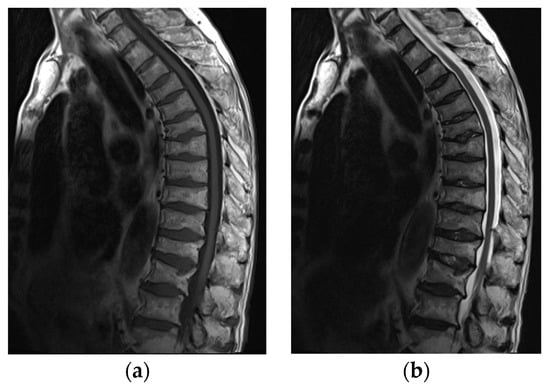

Figure 11.

MRI of the spine in a 61-year-old patient with systemic lupus erythematosus with multiple compression fractures. (a) Sagittal T1-weighted and (b) T2-weighted Time Spin Echo MR images of the thoracic spine show a loss of height in nearly all thoracic and L1 and L2 vertebral bodies without significant bone marrow edema in (b). This is consistent with chronic compression fractures with associated disc dehydration and marginal endplate osteophytes, but without significant retropulsion.